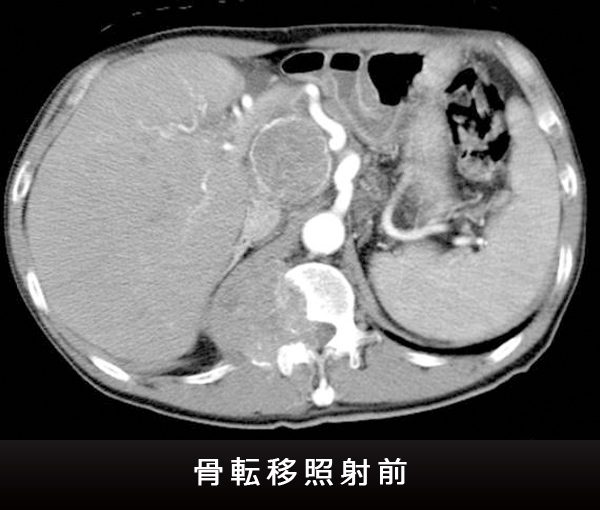

がんによる痛みなどの症状を緩和する目的の放射線治療です。鎮痛剤と異なり、痛みの根本原因を治療するので、副作用は少なく効果は強力です。

熊本大学病院放射線治療科では、地域がん診療連携拠点病院として、他の診療科や地域の医療機関と連携し、緩和的放射線治療にも力を入れています。